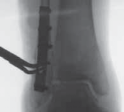

TECHNIQUES B TECH FIG 5 • Direct posterior plating is well

---

C

suited for fractures involving large portions of the posterior malleolus.

A.

Postreduction lateral radiograph showing a posterior malleolus fracture involving more than one third of the articular surface.

B.

Patient in prone position, incision between Achilles and posterior fibula border.

C.

Access is via the interval between the flexor hallucis longus and the peroneal muscle belly. D. Posterior malleolar fragment following A D fibular plating. POSTERIOR MALLEOLUS FIXATION 1. If an adequate reduction can be achieved via closed, indirect reduction, the fracture can be stabilized with cannulated lag screws placed in the anterior-to-posterior direction.